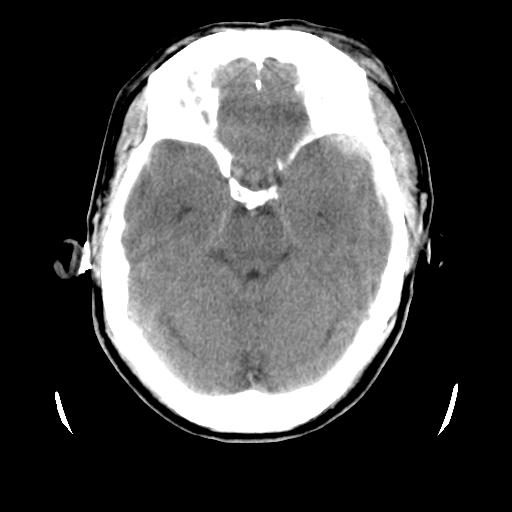

男,51岁,头外伤一小时,呕吐两次。

1)左侧中颅窝蝶骨翼后方硬膜外血肿。2)左侧颞顶部硬膜下血肿。3)蛛网膜下腔出血。4)左侧筛窦及双侧蝶窦炎症(或积血)。5)左侧额部头皮软组织肿胀。